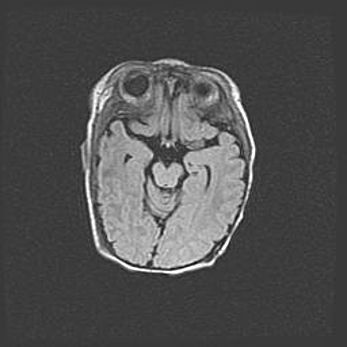

Неполная лизэнцефалия (пахигирия). Открытая гидроцефалия.

Возраст: 17 дней

Вес: 3110 г

Пол: мужской

Окружность головы: 33,5 см

Срок гестации: 35-36 недель

Лизэнцефалия—недоразвитие корковой пластинки и мозговых извилин в результате нарушения миграции нейронов коры. Поверхность мозговых полушарий гладкая. Микроскопически выявляется отсутствие нормальных слоев коры и скопление групп нейронов в подкорковом белом веществе.

Пахигирия—уменьшение числа вторичных извилин. В пораженном полушарии нервные клетки образуют толстый недифференцированный слой с неправильно расположенными нервными волокнами и группами гетеротопных клеток. Нервные клетки незрелые. Белое вещество истончено. При этом нередко аномально развит корково-спинномозговой путь.